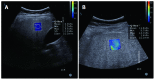

Nonalcoholic fatty liver disease (NAFLD) is a frequent cause of chronic liver diseases, ranging from simple steatosis to nonalcoholic steatohepatitis (NASH)-related liver cirrhosis. Although liver biopsy is still the gold standard for the diagnosis of NAFLD, especially for the diagnosis of NASH, imaging methods have been increasingly accepted as noninvasive alternatives to liver biopsy. Ultrasonography is a well-established and cost-effective imaging technique for the diagnosis of hepatic steatosis, especially for screening a large population at risk of NAFLD. Ultrasonography has a reasonable accuracy in detecting moderate-to-severe hepatic steatosis although it is less accurate for detecting mild hepatic steatosis, operator-dependent, and rather qualitative. Computed tomography is not appropriate for general population assessment of hepatic steatosis given its inaccuracy in detecting mild hepatic steatosis and potential radiation hazard. However, computed tomography may be effective in specific clinical situations, such as evaluation of donor candidates for hepatic transplantation. Magnetic resonance spectroscopy and magnetic resonance imaging are now regarded as the most accurate practical methods of measuring liver fat in clinical practice, especially for longitudinal follow-up of patients with NAFLD. Ultrasound elastography and magnetic resonance elastography are increasingly used to evaluate the degree of liver fibrosis in patients with NAFLD and to differentiate NASH from simple steatosis. This article will review current imaging methods used to evaluate hepatic steatosis, including the diagnostic accuracy, limitations, and practical applicability of each method. It will also briefly describe the potential role of elastography techniques in the evaluation of patients with NAFLD.